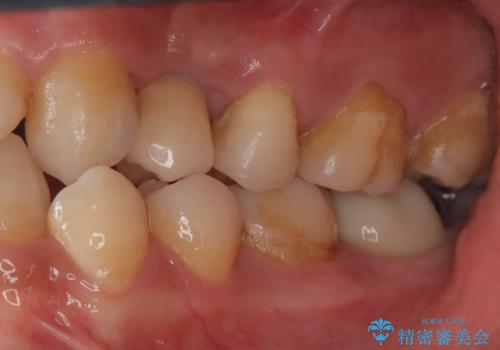

虫歯がかなり進行していて根っこしか残っていない状態でした。日々の歯ブラシが上手く出来ていなくプラーク(細菌の塊)も溜まっている状態でした。

歯を保存するのは出来ないと診断し抜歯した後にインプラントで治療を行いました。